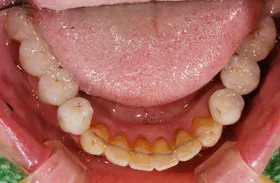

■治療前

■治療後

| 主訴 | しっかりかみたい(咬合障害) |

| 治療方法 | 費用を抑える為、全てインプラントではなく、インプラントを土台とした入れ歯の治療 |

| 治療期間 | 約6か月 |

| 通院回数等 | 約20回 |

| 費用 | 約150万円 |

| リスク・副作用 | 術後の腫れ・痛み |